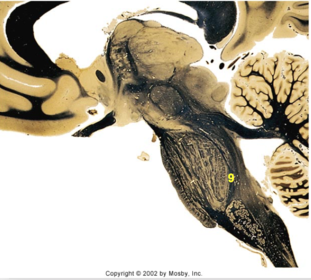

| Superior colliculus | |

| Inferior colliculus | |

| Periaquaductal gray | |

| Pons | |

| Dorsal funiculus | |

| MLF | |

| Red nucleus | |

| Mammillary body | |

| Pineal body | |

| Posterior commissure | |

| Anterior commissure | |

| Thalamus |